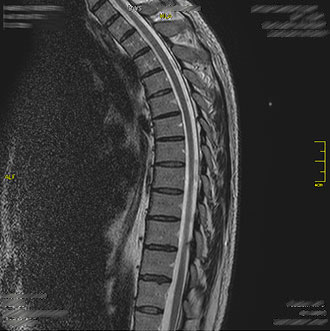

Im Kernspin Zentrum Köln werden alle Abschnitte der Wirbelsäule – Hals-, Brust-, Lenden- sowie Kreuzbeinregion – mit modernster Magnetresonanztomographie untersucht.

Die MRT bietet eine strahlungsfreie und hochauflösende Darstellung von Bandscheiben, Wirbelkörpern, Nerven und dem Rückenmark.

Die MRT der Brustwirbelsäule dient der Abklärung von Schmerzen im mittleren Rücken oder im Brustbereich.

Sie wird im Kernspin Zentrum Köln eingesetzt bei Fehlstellungen, Entzündungen, Tumorsuche oder Bandscheibenvorfällen.

Auch Rückenmarkserkrankungen wie Myelitis oder Syringomyelie können dargestellt werden. Typische Symptome wie ausstrahlende Schmerzen im Brustkorb (Intercostalneuralgie) lassen sich durch die MRT präzise diagnostizieren.